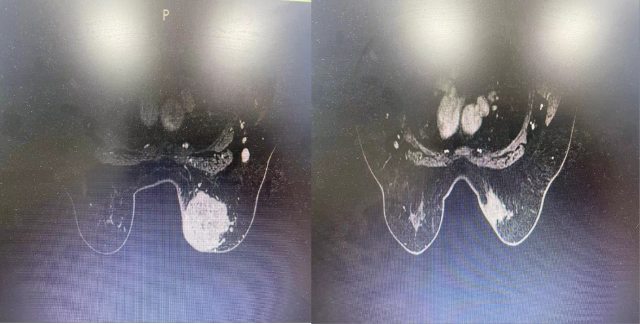

2021-08-06 乳腺增强 MRI 示:右乳占位,考虑乳腺癌,并累及右侧乳头,伴右腋下淋巴结转移;左腋下散在小淋巴结。

2021-11-08 乳腺增强 MRI 示:「右乳腺癌新辅助化疗后」复查:与 2021.8.7 日片比较,右乳肿物较前明显缩小,ADC 值较前升高,早期强化率较前较低,多点 测量时间-信号强度曲线呈缓慢上升,右腋下淋巴结转移较前减小;建议结合临床对比前片。

2021-11-08 乳腺增强 MRI 示:“右乳腺癌新辅助化疗后” 复查:与 2021.8.7 日片比较,右乳肿物较前明显缩小,ADC 值较前升高,早期强化率较前较低,多点 测量时间-信号强度曲线呈缓慢上升,右腋下淋巴结转移较前减小;建议结合临床对比前片。